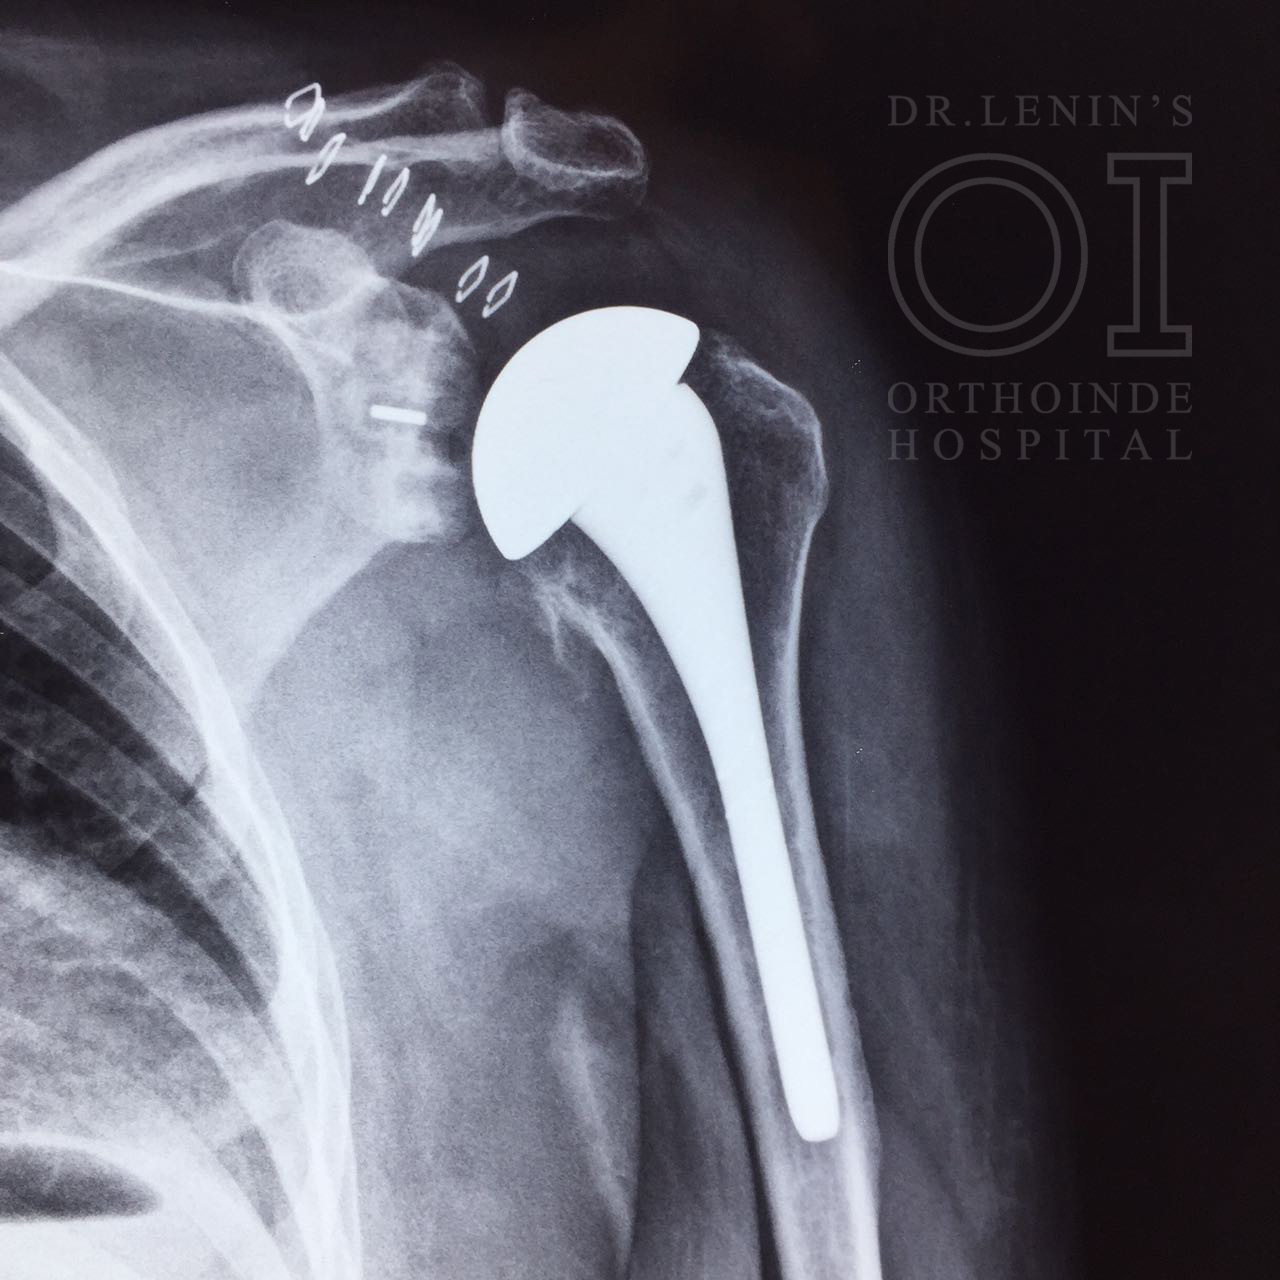

Shoulder hemiarthroplasty is a shoulder replacement in which the damaged humeral head is replaced with a prosthetic humeral head. Shoulder arthroplasty is a rapidly evolving area of orthopedics focused on treating specific, painful ailments of the glenohumeral articulation.

Total Replacement

The standard total shoulder replacement involves replacing the arthritic joint surfaces with a highly polished metal ball attached to a stem, and a plastic socket.

These components come in various sizes. They may be either cemented or press fit into the bone. If the bone is of good quality, we can use a non-cemented (press-fit) humeral component. If the bone is soft, the humeral component may be implanted with bone cement. In most cases, an all-plastic glenoid (socket) component is implanted with bone cement.